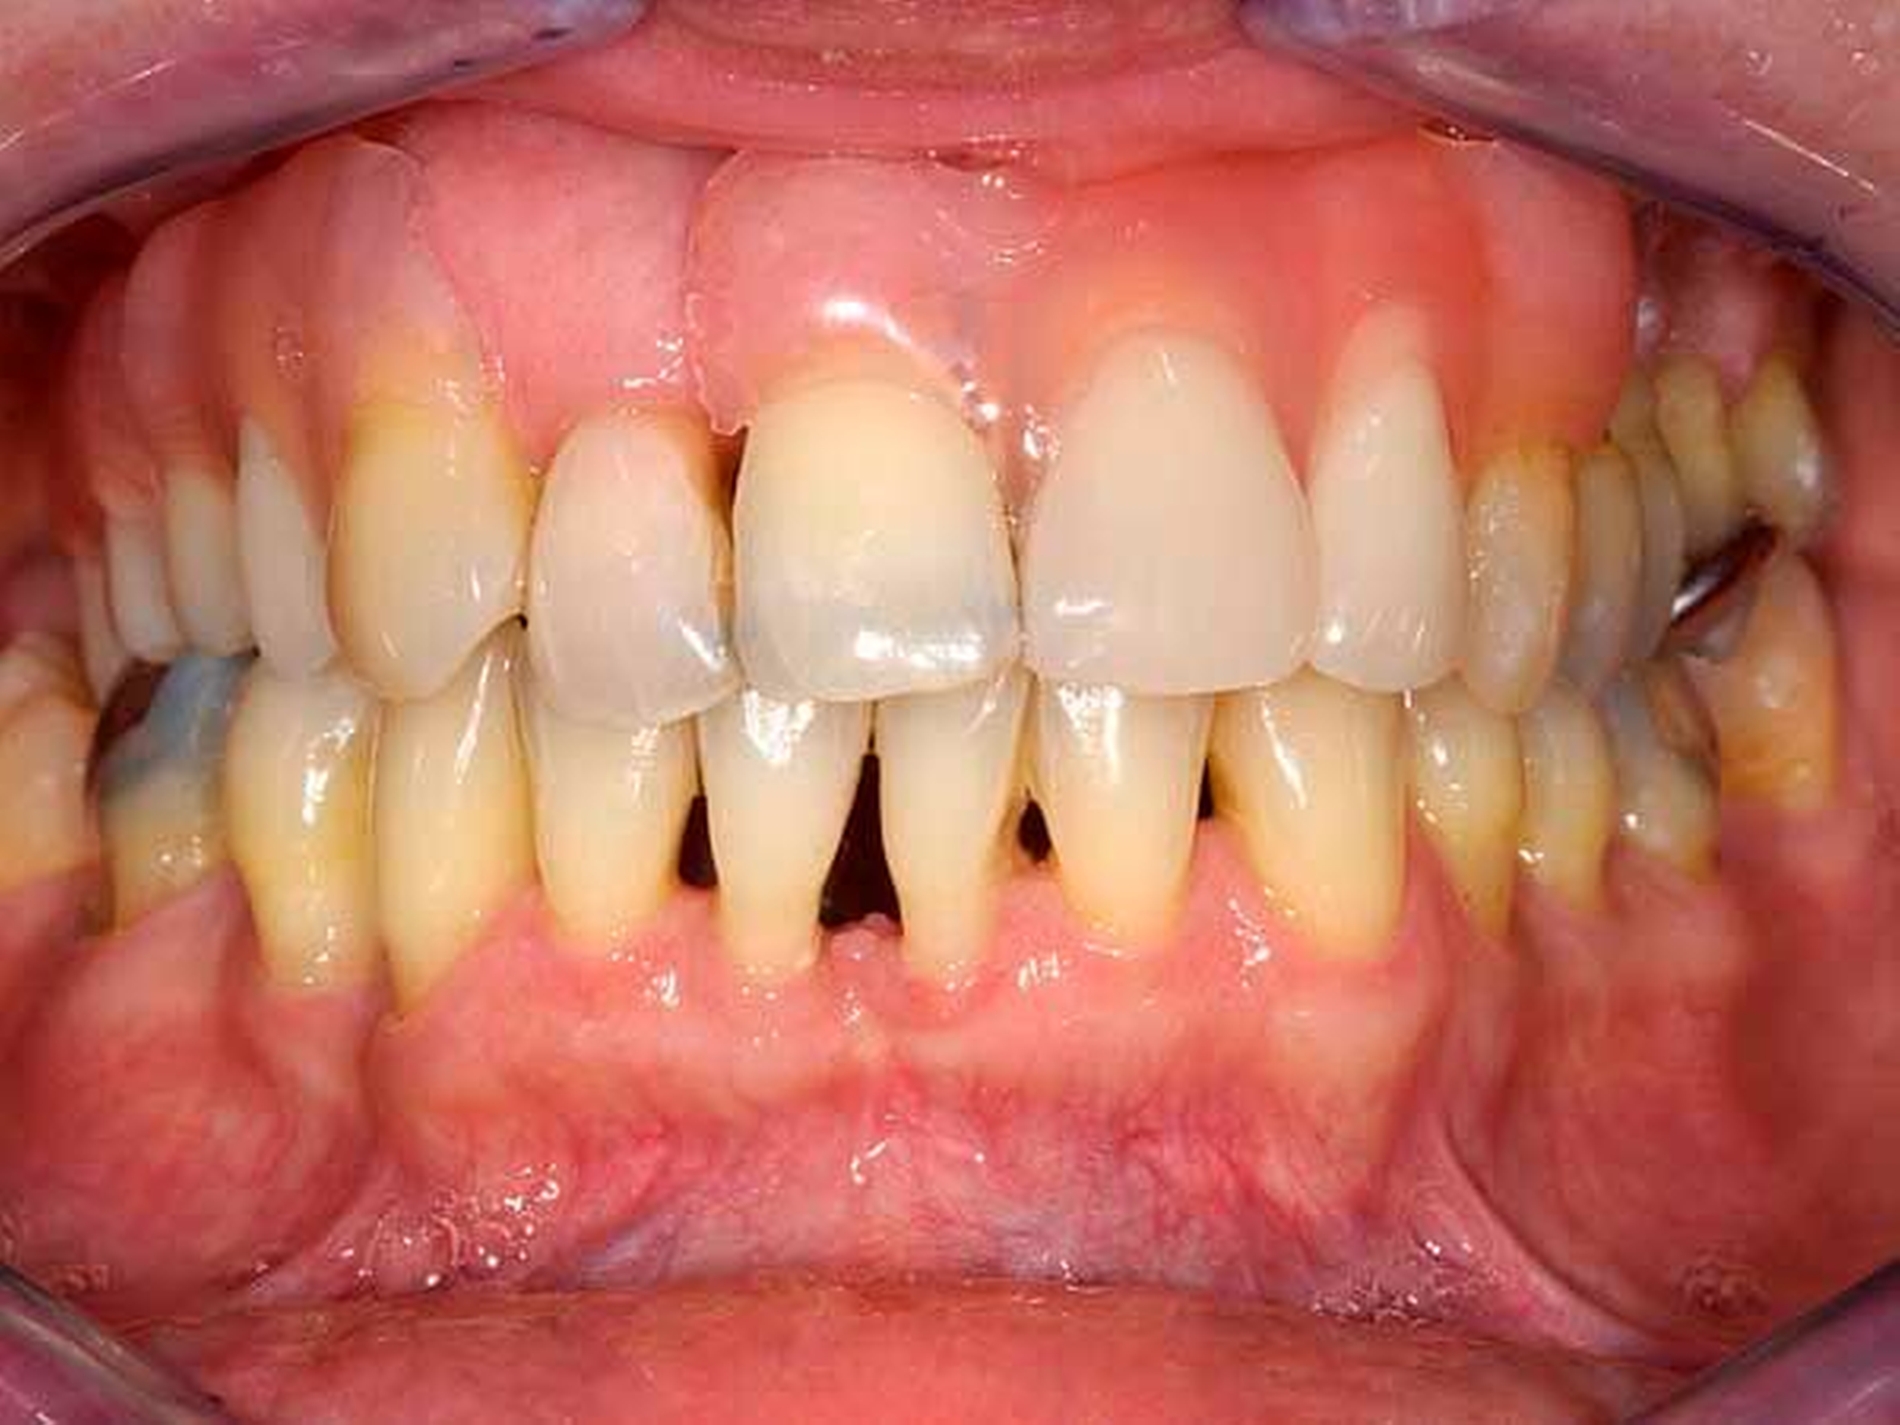

Das Orthopantomogramm (Abbildung 17) zeigt die Gebisssituation einer 49-jährigen Patientin nach Abschluss einer parodontalen Vorbehandlung. Die sehr gepflegte Patientin betreibt eine intensive Mundhygiene, legt hohen Wert auf ihre äußere Erscheinung. Ihre finanzielle Limitation lässt aber keine implantatprothetische oder aufwendige kombiniert festsitzend-herausnehmbare Versorgung zu. Da die Patientin eine hohe Lachlinie hat und eine Demaskierung durch sichtbare Gussklammern im Bereich der Frontzähne fürchtete (Abbildung 18), verweigerte sie konventionellen gussklammerverankerten Zahnersatz und trug entgegen ausdrücklichem zahnärztlichem Rat dauerhaft eine rein schleimhautgelagerte Teilprothese. Die Patientin wurde mit der Bitte um Beratung und Behandlungsübernahme an unsere Einrichtung überwiesen.

Diese Patientin konnte an unserer Einrichtung mit der Modifikation eines gussklammerverankerten Zahnersatzes versorgt werden, bei dem die anterioren sichtbaren Klammer-Retentionsarme aus dem gingivafarbenen Kunststoff Polyamid-12 (Valplast) angefertigt wurden (Abbildungen 19 und 20). Die Polyamidretentionarme müssen aufgrund des wesentlich geringeren Elastizitätsmoduls gegenüber einer CoCrMo-Legierung wesentlich breiter gestaltet werden. Sie liegen allerdings nur den vestibulären Flächen der Ankerzähne an und sind unter der partiell mitbedeckten Gingiva hohlgelegt (Abbildung 21).

Das metallische Gerüst der Teilprothese ist bis auf den Verzicht der anterioren Retentionsarme konventionell mit großem Verbinder, kleinen Verbindern, oralen Klammerarmen und Auflagen gestaltet, posterior findet eine konventionelle Ney-Klammer #1 Anwendung. Die Patientin ist mit dem ästhetischen Ergebnis zufrieden. Inzwischen konnte eine Reihe Patienten mit ähnlicher ästhetischer Problematik versorgt werden (Abbildung 22).

Definitiver Zahnersatz, aus Polyamid-12 (wie Valplast, Sunflex und mehr) gefertigt, gilt in der deutschen Zahnmedizin als obsolet, da der elastische Prothesenkörper durch ungünstigere Lastverteilungen wahrscheinlich die Resorption der knöchernen alveolären Strukturen begünstigt [Blankenstein, 2009] und ist durch die gesetzlichen Krankenkassen nicht erstattungsfähig. Auf den hier angefertigten Zahnersatz treffen diese beiden Einschränkungen nicht zu. Große wie kleine Verbinder, orale Klammerarme und -auflagen sind in üblicher Dimensionierung starr in einer CoCrMo-Legierung ausgeführt. Sie garantieren eine identische Biodynamik bezüglich Abstützung, Sicherung gegen horizontale Schübe, reziproker Wirkung, Kraftableitung ins Gaumengewölbe und starrer Kopplung der Kieferhälften und erfüllen somit die Bedingungen der erstattungsfähigen Regelversorgung. Lediglich die elastischen Retentionsarme und die Kunststoffanteile des Sattels sind aus Polyamid-12 gefertigt.